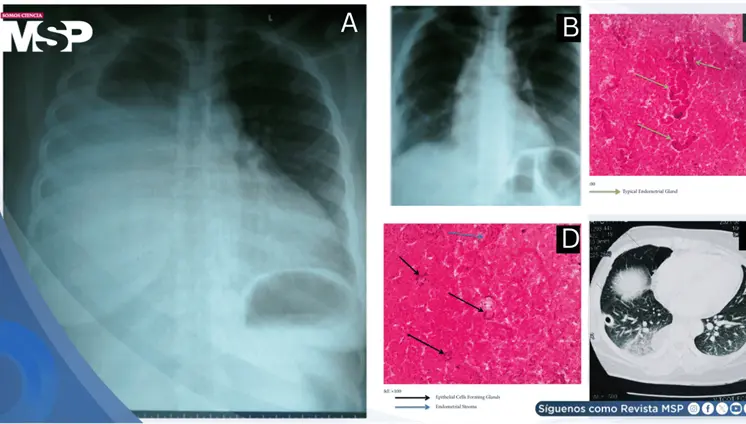

Lo que comenzó como un cuadro frecuente de dolor pélvico y dismenorrea en una mujer, terminó siendo un carcinoma folicular originado en estruma ovárico maligno. La paciente tenía solo 35 años, marcadores tumorales completamente normales y ninguna alteración tiroidea.

El estudio histológico confirmó un adenocarcinoma mucinoso de células en anillo de sello de vejiga con invasión muscular y diseminación metastásica pulmonar y ósea.